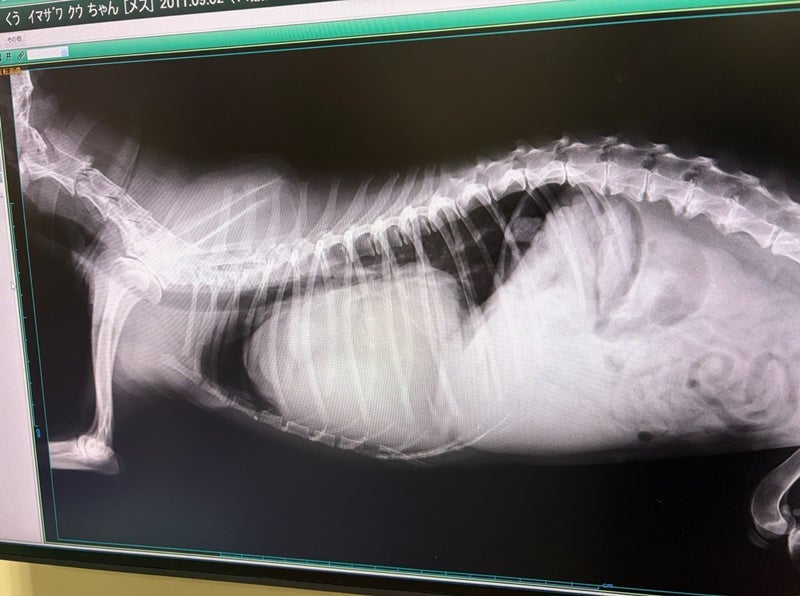

検査では、心臓の拡大や心臓の周りに

液体が溜まっていたこと、右心房の虚脱が

確認され、急性の心不全に近い状態だったと

考えられています。

検査の結果、心臓に腫瘍がありました。

14歳半でこの世を去ったくうの急死の原因は、

心臓の腫瘍によって心臓が大きく膨れ、

酸素を運ぶ力が低下したことによるものと

説明を受けています。